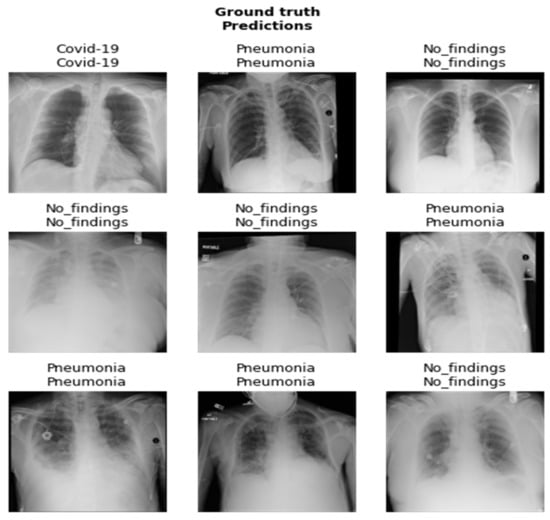

In our research, the dataset utilized for the study consists of X-ray images prepared by integrating images from two different data sources that were used to detect COVID-19 infection. The first dataset comprises COVID-19 X-ray images developed by Cohen et al. [28], including images retrieved from several open-access resources. Also, this source regularly updates images shared by several researchers from different regions. This dataset currently contains 127 X-ray images diagnosed with COVID-19. This dataset consists of 43 female and 82 male patients diagnosed as COVID-19 positive. The second dataset incorporates chest X-rays by Wang et al. [29] that contains normal and pneumonia images. These data sources were integrated and utilized by Ozturk et al. [30,31]. They utilized 500 images of healthy lungs and 500 with pneumonia on frontal chest X-ray images. The images were selected randomly. This was done to prevent the challenge of unbalanced data. In our approach, 100 images from each group include COVID-19, no findings, and pneumonia. A few images of the dataset are shown in Figure 2.

Figure 2. Dataset images.